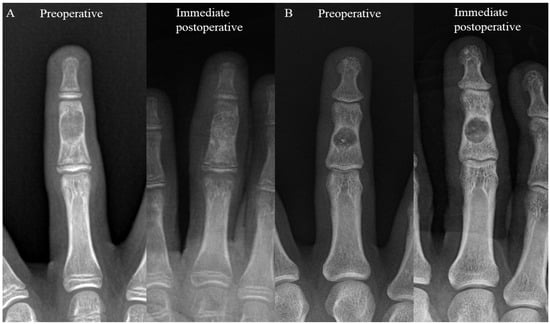

In this retrospective study, medical records were reviewed to identify patients with histologically confirmed solitary enchondroma of the hand who underwent simple curettage followed by impaction grafting with allogenic cancellous bone chips between January 2010 and July 2020. The inclusion criteria were (1) histologically confirmed solitary enchondroma, (2) having undergone simple curettage followed by impaction grafting using allogenic cancellous bone chips, and (3) a minimum postoperative follow-up of one year. The exclusion criteria included (1) patients with multiple lesions, (2) those diagnosed with malignancies such as low-grade or high-grade chondrosarcoma, and (3) patients lost to follow-up. The patients were categorized into two groups based on the extent of bone defect filling post curettage identified in radiographs. Group 1 included those with complete filling, defined as more than 90% of the cavity being filled, while Group 2 included those with incomplete filling, defined as less than 50% of the cavity being filled (Figure 1) [14].

Figure 1. This is an enchondroma of the middle phalanx of the lt 3rd finger treated via curettage and allogenic cancellous bone chip impaction grafting. (A) A 14-year-old male patient who underwent curettage and complete filling, categorized as Group 1. (B) A 28-year-old male patient who underwent curettage and had less than 50% (i.e., incomplete) of the affected area filled, categorized as Group 2.